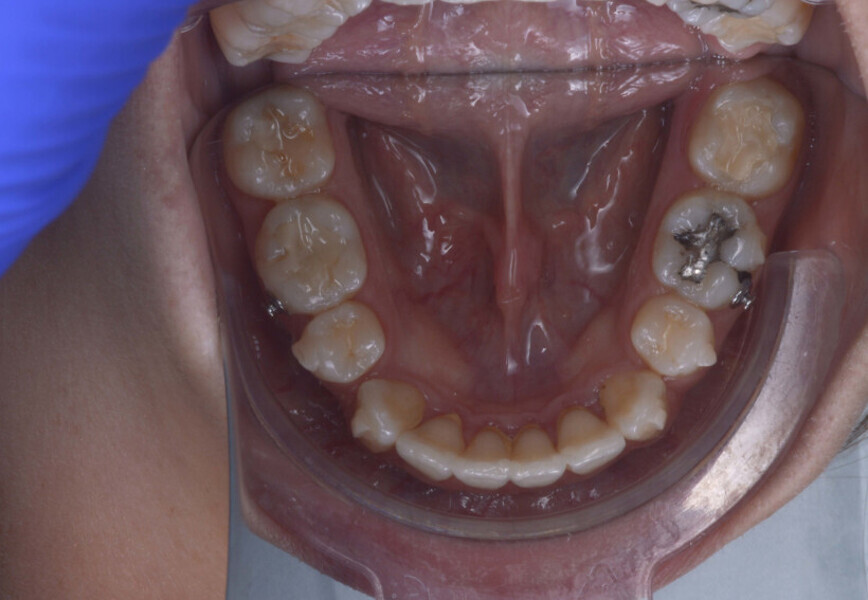

A 35-year-old female patient presented with crowding, muscle and joint pain, and headaches upon awakening. Examination found a skeletal Class I with crowding and bimaxillary protrusion. Facial examination showed a convex profile with protruded lips and a square face shape, intensified on smiling (Figs. 1–4). She reported bruxism, and bilateral masseteric hypertrophy was observed, but there was no alteration of the temporomandibular joints.

Before the aligner treatment began, the maxillary and mandibular second premolars were extracted to create space. With orthodontic treatment, distalisation of the anterior teeth was achieved by employing maximum mandibular anchorage and moderate maxillary anchorage (Figs. 5–7). At the end of the treatment, a stable bilateral Class I occlusion had been achieved, as well as normal inclination and retrusion of the anterior teeth, consequently improving the profile (Figs. 8–10).